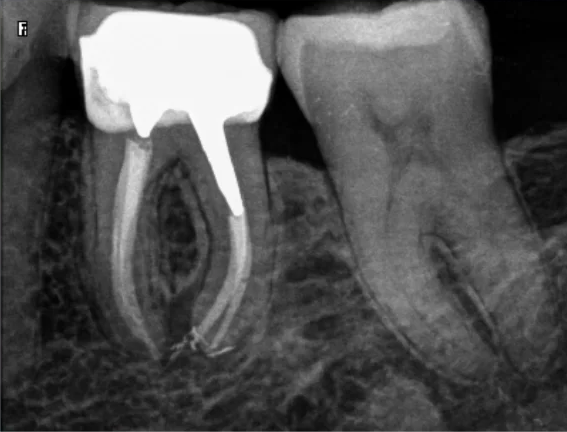

Question 21: What option is can be selected for distal tooth # 4.6?

Question 22: Which surface shows defective restoration?

Question 23: Which surface shows overhang?

Question 24: Which surface shows defective restoration?

Question 25: Which surface shows open margin?

Question 26: What option cannot be selected for mesial tooth surface # 2.8?

Question 27: What options cannot be seen in this X ray?

Question 28: What is the best option that describe distal surface of tooth # 3.5?

Question 29: What options cannot be seen in this X ray?

Question 30: What options can be selected for the tooth # 4.2?